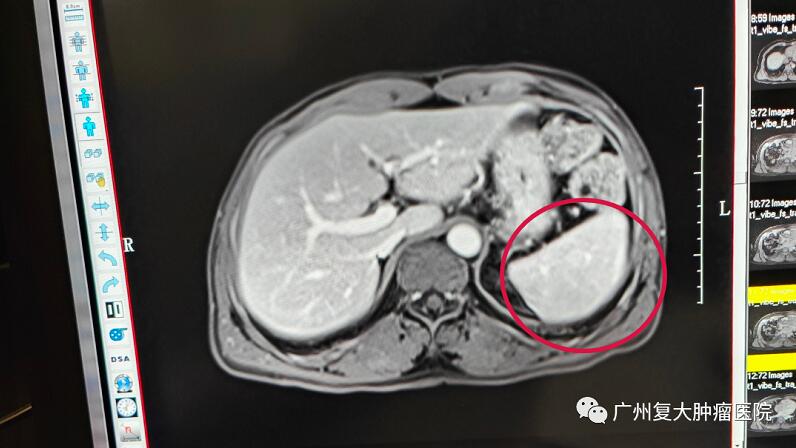

带着惴惴不安的心情,小伙子来到广州复大肿瘤医院就诊。入院后检查发现其彩超结果提示,左侧肾上腺区可见低回声肿物,边界清,内回声均匀,双肾血流灌注良好。为进一步诊断,小伙子又接受了上腹部MRI平扫+增强+DWI检查,脾脏缺如,脾脏术区可见大小约65×52×56mm团块灶,其内可见脾动静脉走行。

了解到患者几年前曾因车祸造成脾脏破裂,做过脾脏切除术,放射科李忠海主任结合影像结果及既往病史,认为该肿块并非肿瘤,而是副脾或残余脾脏代偿性增大。

95%位于脾脏周围,尤其是脾门部,也可位于盆腹腔,甚至生殖器附近,容易同肿大淋巴结、胰腺、肾脏器官的肿瘤混淆。一般声像图表现为脾门附近呈近似圆形或椭圆形的实质肿块,边界清晰,包膜光整,内部为均匀细点状回声,回声强度与脾相似,但与脾分界清楚、部分副脾有与脾门动静脉相通的血管分支。